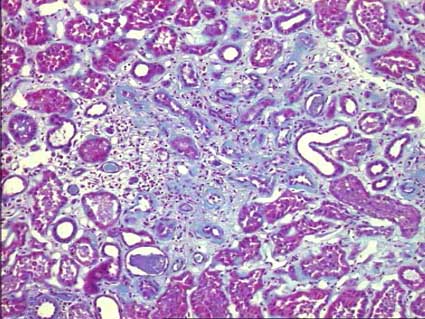

Figura 14. La NCT se caracteriza por cambios crónicos en todos los compartimentos histológicos del tejido renal. Es un cambio inespecífico en el que es muy importante tratar de determinar su causa. El grado de FI/AT se determina, principalmente, por el porcentaje de fibrosis intersticial. (Tricrómico de Masson, X200).